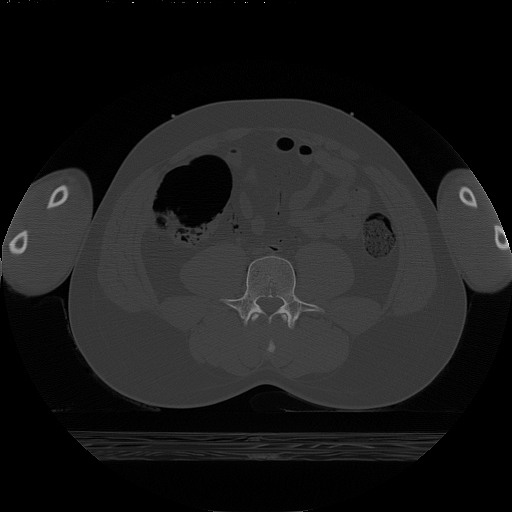

CT scan of Abdomen and Upper Limb

TUSM Dept. of Anatomy and Cellular Biology 11/19/96